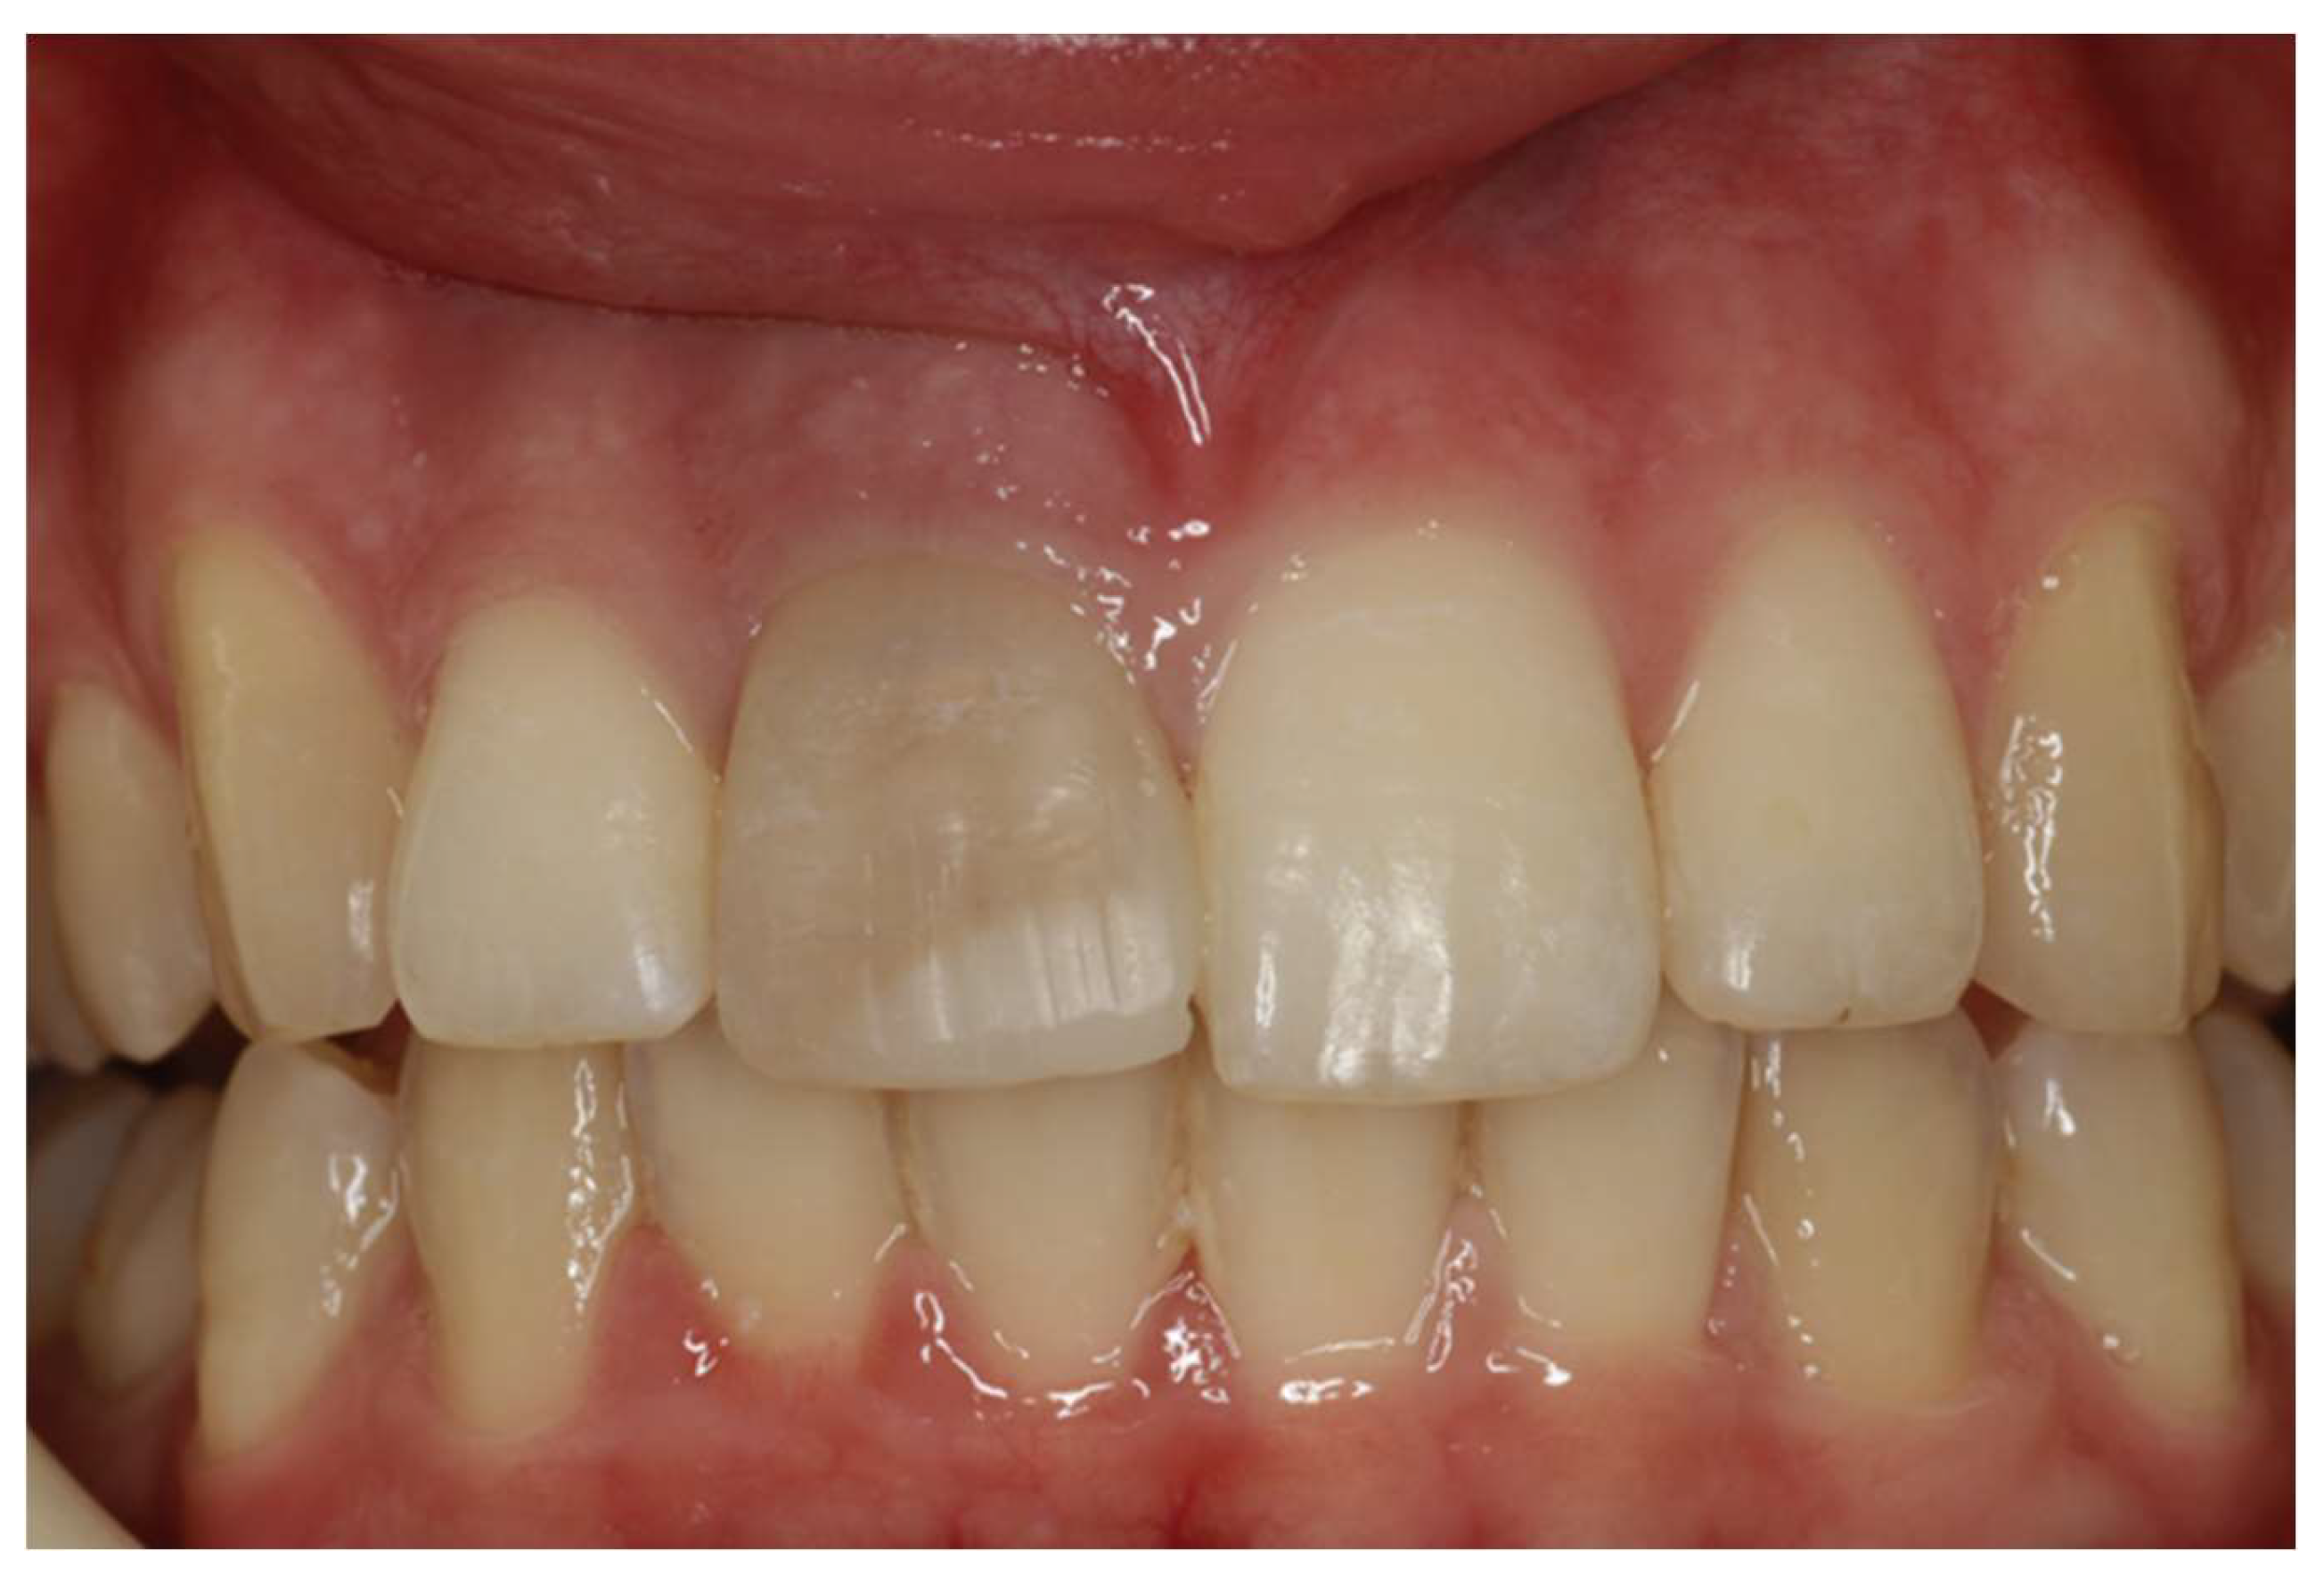

2. Clinical Case

- For better aesthetic results, in cases of intrinsic discoloration, an internal tooth whitening procedure may precede.